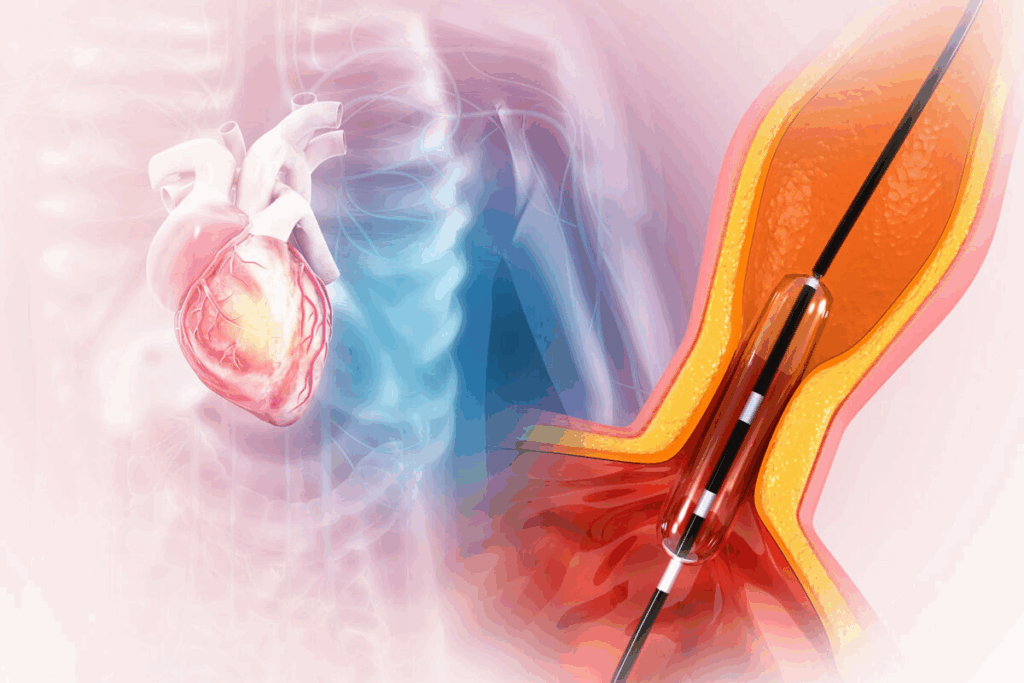

Learning about angioplasty and stent placement can ease worries and help with recovery. These procedures aim to fix blocked or narrowed heart arteries. This helps blood flow back to the heart.

What Happens During the Procedure

A thin, flexible tube called a catheter is used. It goes through an artery in the groin or arm to the blocked artery. A coronary stent, a small mesh tube, is then placed to keep the artery open. This improves blood flow to the heart muscle.

The procedure is done under local anesthesia. Patients are usually awake. The goal is to improve blood flow and reduce symptoms like chest pain.